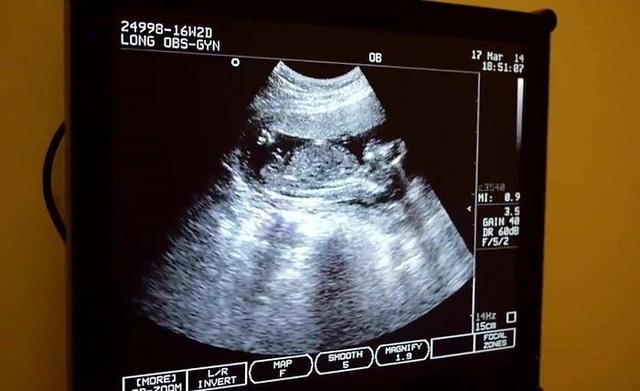

首先是超声波诊断,也就是B超。

超声诊断是一种非侵入性的方法,比较安全也比较准确,通常在怀孕第18周至第22周之间进行。但如果胎儿的位置不理想,医师在进行超声波诊断时也会受到干扰,可能检测不出准确的性别。在这种情况下,可以过段时间再来扫描预测一次。